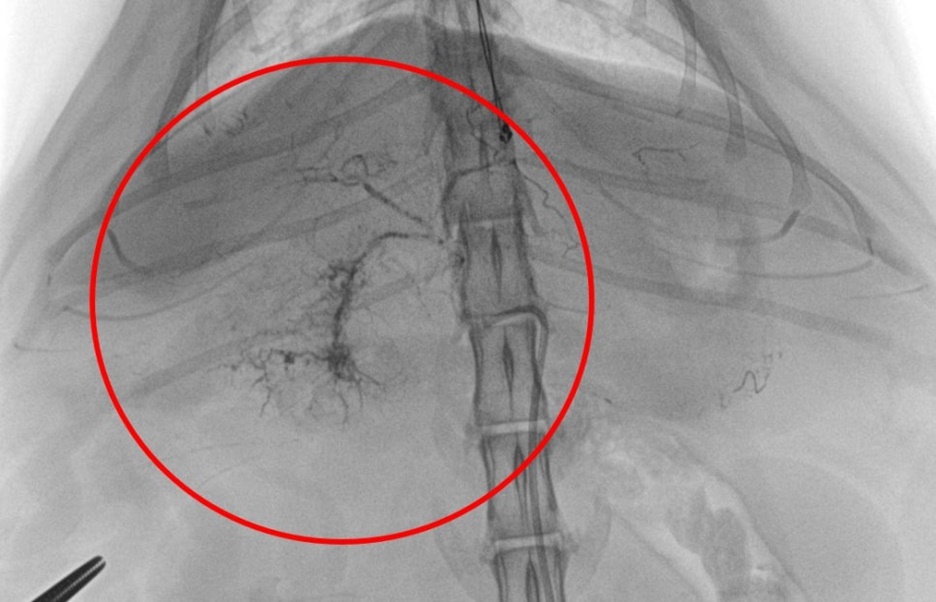

▲ 시술을 위해 대퇴동맥으로 접근합니다. 대략 2-3cm 정도의 절개가 필요합니다. 대퇴동맥을 확보한 뒤 동맥 카테터를 설치하여 고양이 간종양으로 접근할 준비를 합니다.

▲ 혈관 조영을 통해 주행 방향을 확보하고 혈관 색전 전용 투시기(Fluoroscopy)를 이용하여 간종양의 영양 동맥(Feeding artery)에 접근합니다.

▲ 간종양의 영양 동맥(Feeding artery)에 항암물질과 색전 물질을 투여합니다. 조영제를 섞은 항암제와 색전 물질이 투시기를 통해 혈관 내 잘 투여되는 것을 확인합니다.